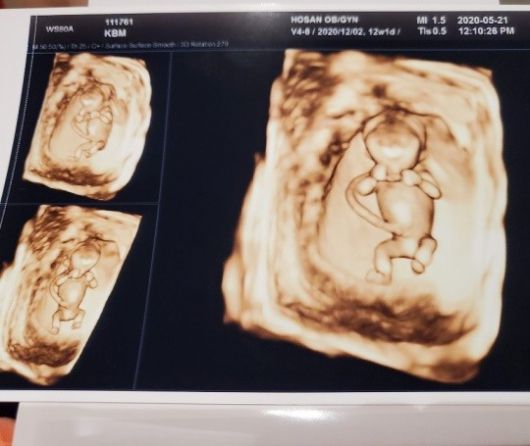

김보미는 12일 자신의 인스타그램을 통해 "13주때인가.?? 입체초음파 처음 해본날~ 신기방기. 이제 15주째 살이찌는건지 배가나오는건지"라는 글과 함께 한 장의 사진을 게재했다.

공개된 사진 초음파 사진으로, 아이가 건강한 모습으로 뱃속에 자리잡은 모습을 확인할 수 있다.